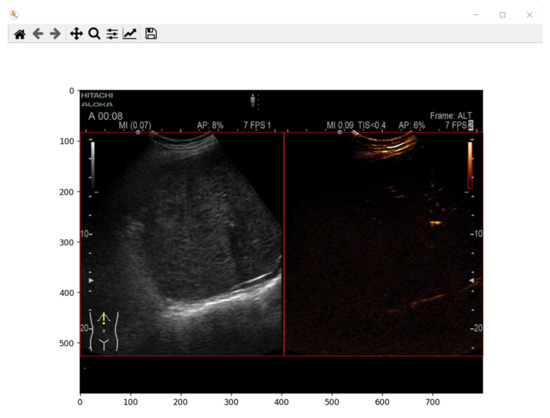

To create the dataset and for extracting the lesion from each frame in the video investigation, boundaries were defined for each region in the video investigation. The boundaries for B-mode image were defined in our previous work [10] and were used to create the dataset but also for predicting the mask. For the contrast image section in the video investigation file, the boundaries were determined experimentally as for the B-mode image. A frame was plotted from a video investigation file, and the minimum and maximum x and y coordinates were defined. The determined values are presented in Table 2. A sample frame with the determined coordinates is presented in Figure 3.

As mentioned earlier, the goal of the present study was to create a system to automatically extract time-intensity curves and predict the malignancy of a lesion from contrast-enhanced ultrasound imaging. Therefore, besides cropping the B-mode and contrast mode images from the video investigation, the color scale was also needed. For each ultrasound device, the color scale is present in the video investigation file. To crop and obtain the color scale, the same principle was applied as for B-mode imaging and contrast mode imaging: experimentally determine the minimum and maximum x and y coordinates. The determined values for the color scale are presented in Table 3. In addition, a sample frame with the determined coordinates is presented in Figure 3.

Figure 3. B-mode, Contrast mode, and color scale coordinates determination from one frame. Each part is marked by a rectangle with red edges.